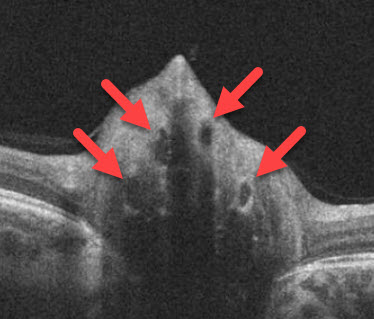

One of the more common conditions that can simulate papilledema is optic disc drusen. Drusen are an accumulation of calcium deposits within the nerve head, giving it a lumpy, irregular and elevated appearance. This is called pseudopapilledema. Drusen may be located near the nerve surface where they appear as yellow round or oval lumps or can be buried deeper in the nerve tissue where they can be very difficult to detect. Drusen generally become more visible with age. Optic disc drusen occasionally run in families as a dominant trait.

Superficial optic disc drusen are often easily found during a dilated eye exam. Buried disc drusen are more difficult to detect. Fundus autofluorescence, ultrasonography, and OCT scanning can be used to help identify buried drusen. However, it is sometimes extremely difficult to tell if a patient has pseudopapilledema from optic disc drusen or true papilledema from a serious medical problem. In these instances, MRI scanning and subsequent lumbar puncture may be necessary.